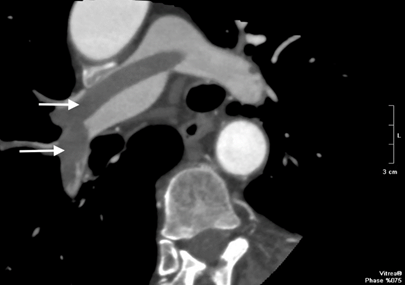

A 76-year-old male with prior systemic hypertension, obesity class III, COPD, and NIDDM presented to the emergency department with acute complaints of worsening dyspnea with cyanosis, tachyarrhythmia - 160 b/min, hypotension - 80 / 60mmHg, D-dimer value -1800 ng/ml. He had undergone an endoscopic cholecystectomy a week before. CT pulmoangiography demonstrated dilated pulmonary trunk with a saddle pulmonary embolism, extending into the left and right pulmonary arteries as in the distal branches (Figure 3). Hemodynamic instability and recent cholecystectomy led us to decide on emergency surgical embolectomy.

Figure 3 CT pulmoangiography - saddle pulmonary thrombosis, proximal and distal pulmonary emboli (white arrows).